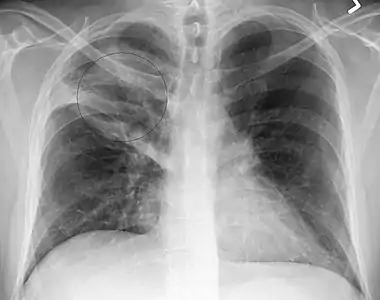

- AP CXR showing right lower lobe pneumonia

- Right upper lobe pneumonia as marked by the circle.